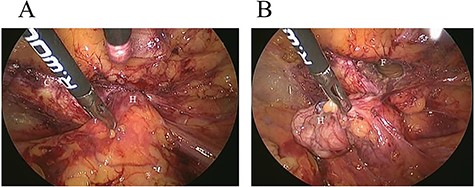

A 62-year-old woman visited our hospital with a 1-day history of lower abdominal pain and bulging from a right groin lesion. Her physical examination showed a right inguinal bulge and pain. Her abdomen was not distended and was without rebound tenderness and muscular defense. However, the bulge in the right groin lesion could not be reduced manually. Contrast-enhanced computed tomography showed a hypodense rounded lesion medial to the right femoral vessels (Fig. 1A) with fluid collection (Fig. 1B), with no intestinal obstruction or ischemia. Based on these physical and radiological findings, the patient was diagnosed as having a right incarcerated femoral hernia containing fat tissue. As there were no clear findings of intestinal obstruction, elective TEP repair was performed 1 day after admission following preoperative evaluation of her general condition. An infra-umbilical incision was made under general anesthesia. The preperitoneal space was created with blunt dissection with the aid of CO2 gas insufflation to a pressure of 12 mmHg. Two 5-mm trocars were inserted into the left mid-abdomen. The hernia sac had herniated into the right femoral canal (Fig. 2A). Therefore, we diagnosed a right incarcerated femoral hernia containing greater omentum. However, there were no findings of abscess formation or small bowel necrosis. We were able to release the hernia sac using laparoscopic forceps (Fig. 2B). After reduction of the hernia sac, 10.3 × 15.7 cm polypropylene mesh was placed in the preperitoneal space and fixed to Cooper’s ligament with a fixation device (ProTack™, COVIDIEN) (Fig. 3). Intraperitoneal observation was not performed because we considered it unnecessary to confirm the presence of intestinal damage. The patient’s postoperative course was uneventful, and she was discharged from our hospital 3 days after surgery. Presently, at 1 month after surgery, the patient is doing well without recurrence or mesh infection.

Intraoperative findings (2). Polypropylene mesh was placed in the preperitoneal space. Hernia sac (H).